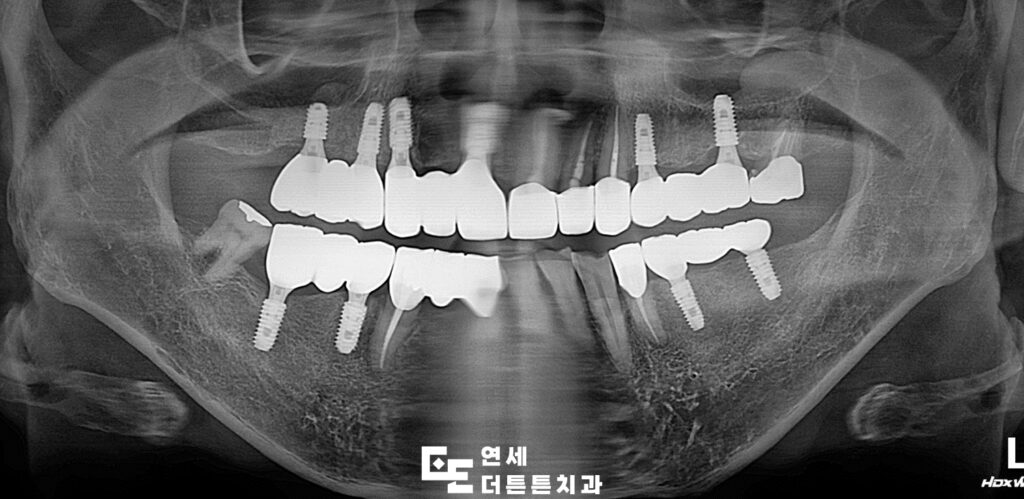

먼저 예후가 좋지 않은 치아들을 발치하고 결손 부위에는 임플란트를 식립하여 기능적인 지지 기반을 형성하였으며 최종 보철물이 들어가기 전 기간동안 사용하실 수 있는 임시틀니를 제작해 드렸습니다. 임플란트가 뼈에 제대로 붙기까지는 시간이 필요하며, 일반적으로 상악은 약 6개월, 하악은 약 4개월이 소요되어 그 기간동안 사용하시며, 최종 보철물에 대한 전반적인 상담도 충분히 진행할 수 있도록 하였습니다.

이후 기존 치아와의 조화를 고려하여 보철 치료를 진행하였습니다. 치료 과정에서는 단순히 치아를 대체하는 것에 그치지 않고, 교합의 균형과 저작 기능 회복, 그리고 자연스러운 외관까지 함께 고려하였습니다. 특히 전치부의 경우 심미적인 요소가 중요한 부위이기 때문에 치아의 형태와 색상, 배열을 세밀하게 조정하여 전체적인 인상이 자연스럽게 개선될 수 있도록 하였습니다.

또한 잇몸 상태 역시 치료 결과에 큰 영향을 미치기 때문에 염증 관리와 위생 상태 개선을 병행하면서 치료를 진행하였습니다. 단계별 치료를 통해 점진적으로 구강 환경을 안정화시키고 최종적으로 기능과 심미를 모두 만족할 수 있는 상태로 마무리하였습니다.